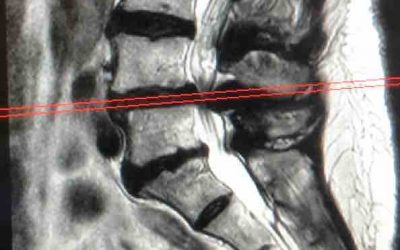

Espondilolistesis: Causas, Síntomas y Tratamientos Efectivos

La espondilolistesis es una afección espinal que puede limitar la movilidad y causar dolor. Un enfoque de tratamiento personalizado es crucial para maximizar la recuperación y mejorar el bienestar de los pacientes.